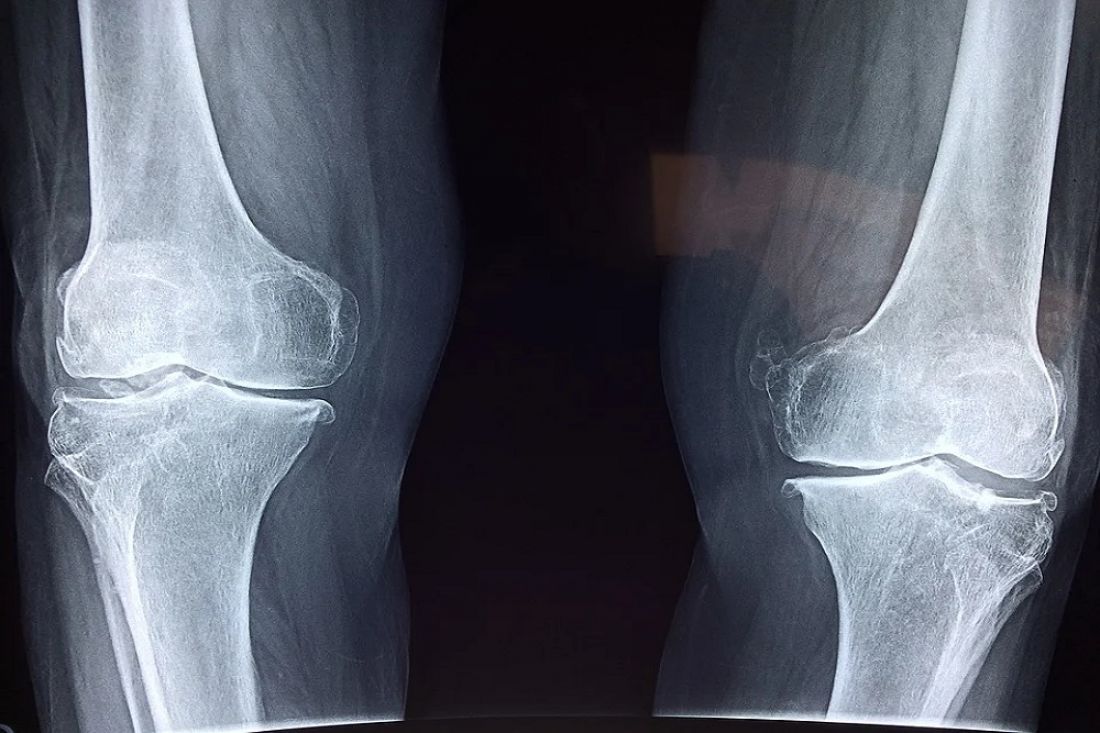

За помощью к пензенским травматологам за неделю обратились более 600 человек

В течение недели – с 11 по 17 января – к пензенским травматологам обратились более 600 человек. Об этом проинформировали представители 6-й городской больницы имени Захарьина.

В травмпункт, расположенный на улице Пионерской, за этот период поступили 435 пострадавших. Также обращения зафиксированы и в травматологическом приемнике стационара больницы. Как сообщается в instagram-аккаунте пензенского медицинского учреждения, туда обратились 195 человек.

44 пациентам потребовалась госпитализация. Отмечается, что 82 человека обратились за квалифицированной помощью с черепно-мозговой травмой.